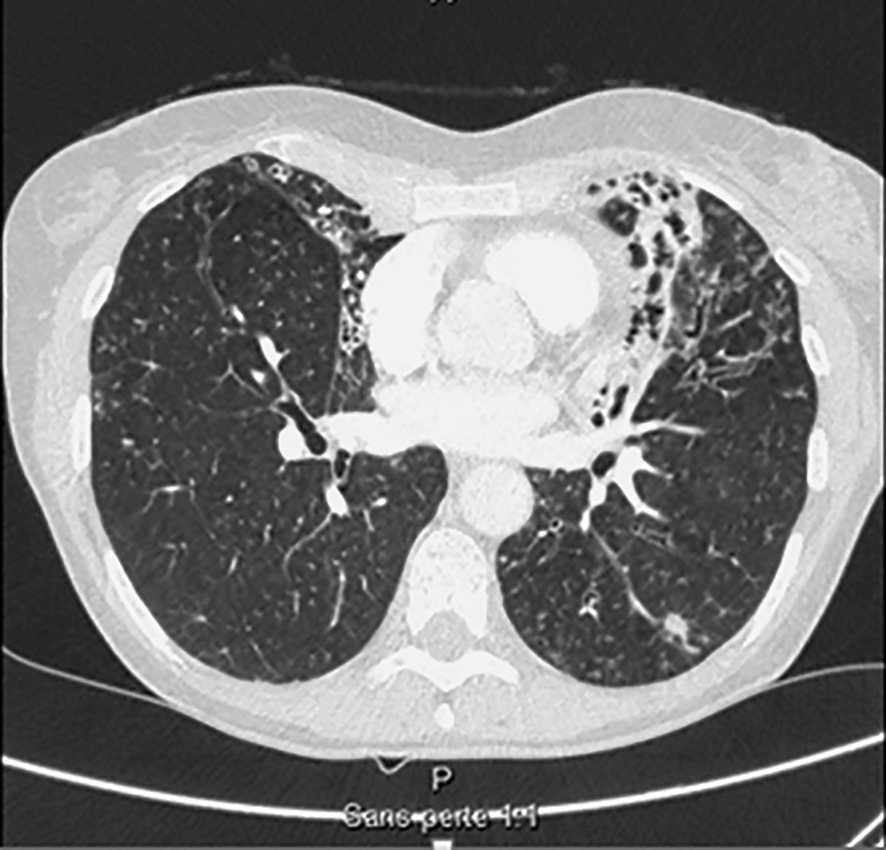

Seul un scanner thoracique haute résolution confirme le diagnostic anatomique : augmentation permanente et irréversible du calibre des bronches sous-segmentaires, cylindriques, variqueuses ou kystiques, localisées à un lobe ou diffuses. On élimine une autre cause de toux chronique comme un cancer bronchique. Toux, expectoration, infections bronchiques répétées + bronchectasies au scanner définissent le syndrome bronchectasique.